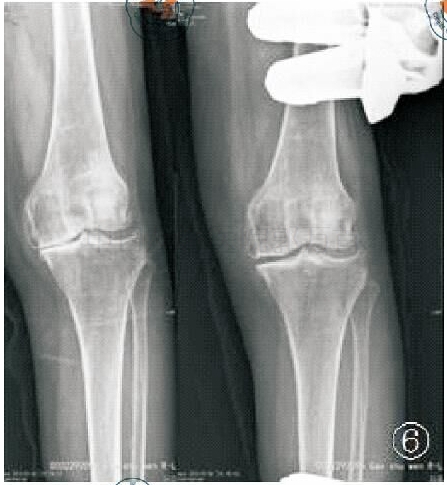

X线片六:术后正位、髌骨轴位、侧位

前后位X线:患者仰卧于 X 线床,双脚并拢,双膝标准正位状,中心线对准髌骨下缘直射入,即以胫骨侧假体关节面为中心照射。侧方X线:患者仰卧于X线床上,屈膝 20°~30°,膝部外侧缘紧靠暗盒,髌骨与暗盒垂直,中心线对准关节线垂直射入,即以股骨部假体为中心。

对于胫骨假体:①在前后位,假体与胫骨轴成角90°(容许5°误差)。其外侧靠近髁间嵴,内侧缘达到胫骨内侧骨皮质,并允许轻度伸出,但不要超出胫骨皮质内侧2 mm。骨—假体界面应该显示出薄层连续骨水泥层并向骨质渗透几毫米。骨水泥在外侧面及龙骨周围渗入的范围比在中间渗入的更深。②在侧位,胫骨假体需要后倾7°,即假体水平面向后下倾斜与胫骨纵轴成7°角(容许5°误差)。假体后缘应该达到后侧皮质,但悬出不超过 2 mm。若悬出过多,可能意味着胫骨假体龙骨槽开槽时损害了胫骨后侧骨皮质。

胫骨假体前后位、侧位示意图

对于股骨假体:①在前后位,假体因为伸直位股骨假体相对于胫骨内旋了15°通常看起来很像一个凹背座椅。在冠状面上,股骨假体中心杆轴线平行于股骨机械轴线,也就是与股骨解剖长轴大约呈7°(容许10°误差),否则股骨假体为内翻或外翻,降低关节面的有效接触面积。②在侧位,假体中央固定柱轴线应该平行于股骨解剖长轴,容许10°以下屈曲及5°以下过伸。

股骨假体前后位、侧位示意图